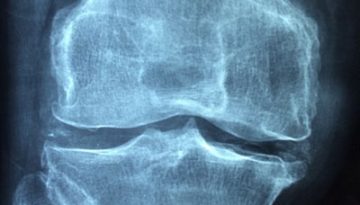

Arthritis Symptoms Are Variable Given The More Than Hundred Different Types Of Arthritis To Check For